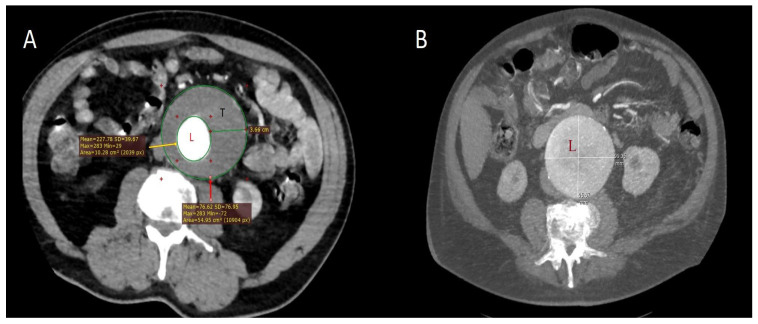

植根后综合征(PIS)是血管内支架植入术(EVAR和TEVAR)后的早期炎症反应,以培养阴性发热和白细胞增多为特征。患者术前的炎症状态被认为在其发展中起核心作用。本研究旨在评估系统性炎症反应指数(SIRI)和嗜酸性粒细胞与淋巴细胞比值(ELR)是否可以作为PIS的术前预测指标。前瞻性记录300例主动脉瓣植入术患者的临床资料和术前24小时、术后24小时、72小时和术后1周的实验室结果。PIS定义为培养阴性发热≥37.8°C,并伴有白细胞计数≥12,000/µL。基于全血细胞计数(SIRI和ELR)的炎症指标,以及血清c反应蛋白(CRP)和白蛋白水平,在PIS患者和非PIS患者之间进行比较。采用Logistic回归和受试者工作特征(ROC)分析确定独立预测因子。55例(18.3%)患者发生PIS。PIS患者更年轻(70.1±8.6岁vs. 72.7±7.3岁;p = 0.042),动脉瘤直径和壁栓厚度更大。术前,PIS患者的白细胞计数、SIRI和CRP水平明显较高,而ELR和白蛋白水平较低。多变量分析显示,较大的动脉瘤直径(OR: 1.2; 95% CI: 1.0-1.3; p = 0.003)、较大的壁栓厚度(OR: 1.3; 95% CI: 1.0-1.6; p = 0.012)、EVAR手术(OR: 3.7; 95% CI: 1.2-6.3; p = 0.033)、较高的SIRI (OR: 1.9; 95% CI: 1.2-3.1; p = 0.005)和较高的CRP (OR: 1.4; 95% CI: 1.1-3.2; p = 0.003)与PIS显著相关。相反,年龄增加、较高的ELR和较高的白蛋白水平与PIS风险降低相关。从标准实验室测试中常规获得的简单生物标志物可以对PIS的术前预测和术后识别做出有意义的贡献。将它们整合到风险分层模型中,并根据明确的诊断标准进行确认,将需要在更大的、多中心的研究中进行验证。